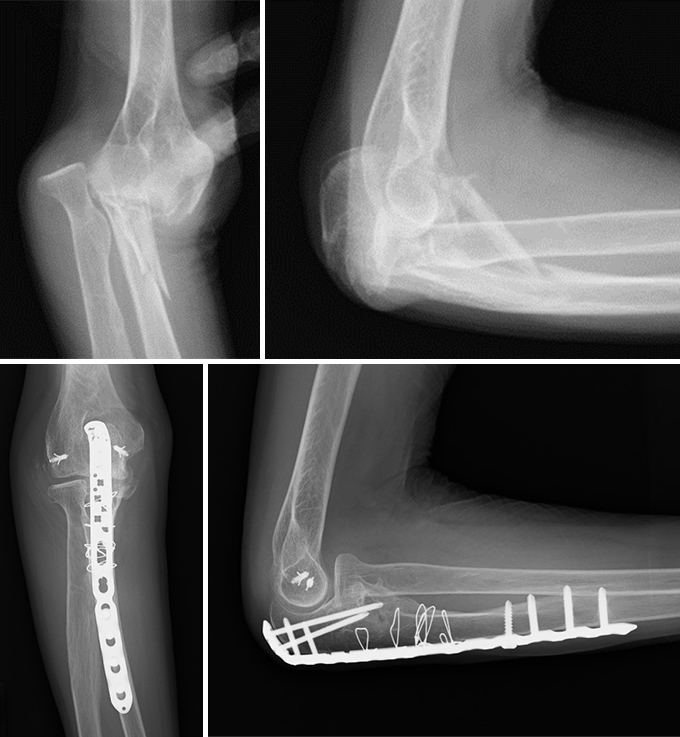

肘頭骨折

肘の尖った部分(肘頭)が折れる外傷で、転倒して肘を強くついた際などに起こります。肘頭には上腕三頭筋が付着しており、牽引によって骨片が離開するため、痛みや腫れが強く、肘を伸ばすことが困難になります。ずれが少ない骨折ではギプス固定で自然治癒を目指しますが、多くの場合は筋力により骨折部が引き離される力が加わるため手術を要します。ワイヤーやプレートで固定する従来の方法に加え、当科では骨折型によって金属を用いずに強力な縫合糸で固定する方法も行っております。強固に固定することで術後早期からリハビリを行い肘の可動域の再獲得を目指します。

症例① 70代 女性 プレート固定

症例② 70代 女性 dual suture fixation